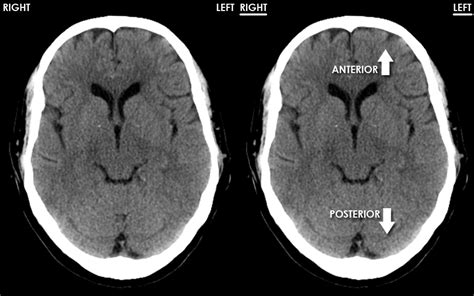

Normal Brain Ct

Understand what a normal brain CT scan looks like and why it is essential for ruling out neurological conditions. This guide explains imaging procedures, how radiologists interpret results, and the diagnostic significance of a clear, healthy scan when evaluating symptoms like headaches or trauma. Learn the importance of diagnostic imaging for accurate health assessments.